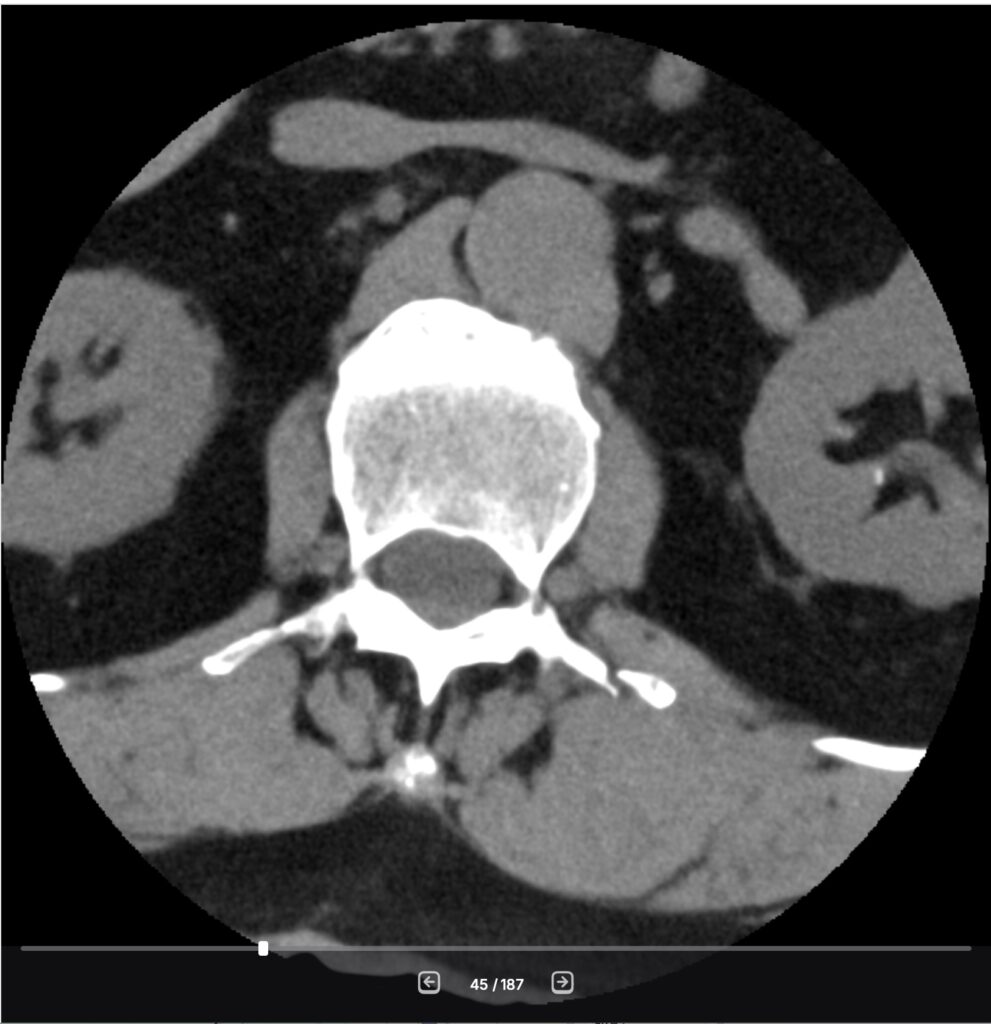

Because this is what you need to do when you have '*minor fractures*' of the transverse processes on your spine, as can be seen in my CT scan after my incident in November.

Those three small fractures in my L1-L3 vertebrae don't care about my great VO2 Max. They don't care that I lifted a quarter-million pounds with my back muscles last year. They don't care that I spent a whopping 729 workouts last year, a combination of actual fitness routines, walking, and skiing.

But if I listen to the engine, I destroy the chassis. That's my back. Those 3 small vertebrae are healing. They're still pretty fragile - I'm told I've got another 3 to 5 weeks to go before they have fully fused and are back to '*normal.*'